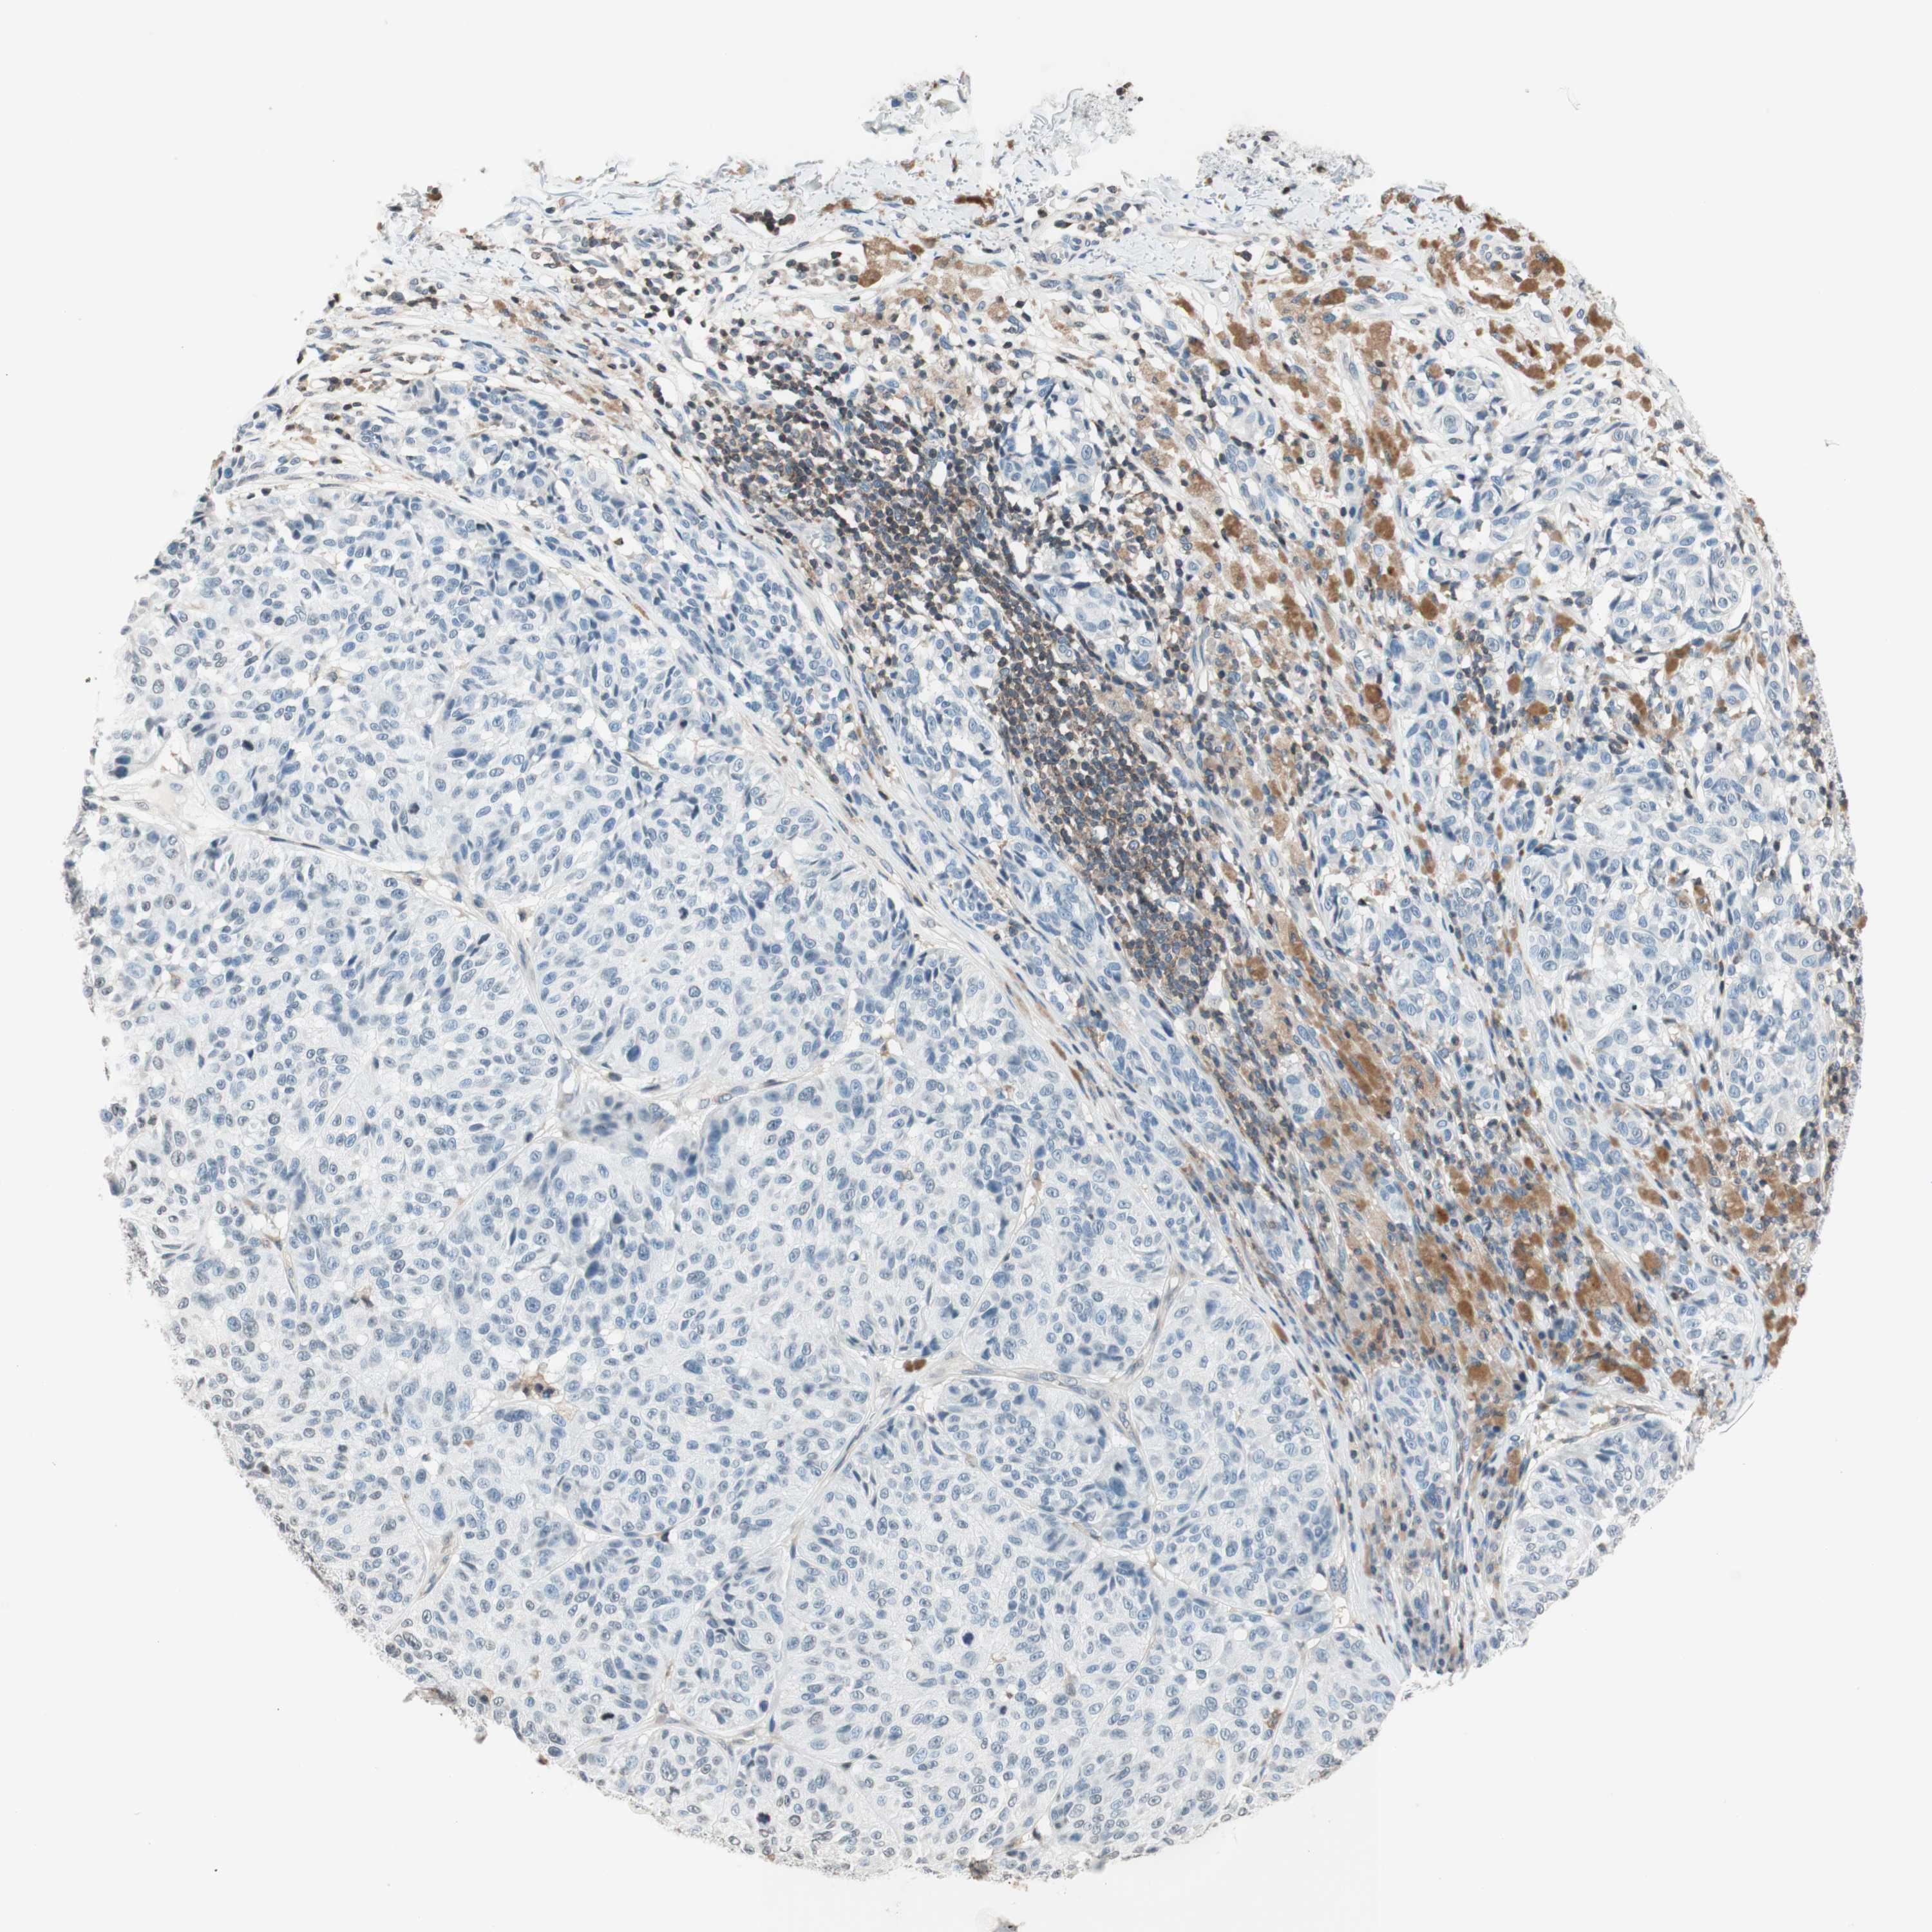

MELANOMA - Protein expressioni

A mouse-over function shows sample information and annotation data. Click on an image to view it in a full screen mode. Samples can be filtered based on level of antibody staining by selecting one or several of the following categories: high, medium, low and not detected. The assay and annotation is described here.

Note that samples used for immunohistochemistry by the Human Protein Atlas do not correspond to samples in the TCGA dataset.

Antibody stainingi

Antibody staining in the annotated cell types in the current human tissue is reported as not detected, low, medium, or high, based on conventional immunohistochemistry profiling in selected tissues. This score is based on the combination of the staining intensity and fraction of stained cells.

Each image is clickable and will lead to virtual microscopy that enables deeper exploration of all samples and also displays staining intensity scores, fraction scores and subcellular localization as well as patient and tissue information for each sample.

Antibody HPA003739

Antibody CAB009737

Staining

High

Medium

Low

Not detected

Intensity

Strong

Moderate

Weak

Negative

Quantity

>75%

75%-25%

<25%

None

Location

Nuclear

Cytoplasmic/membranous

Cytoplasmic/membranous,nuclear

Malignant melanoma, NOS

Malignant melanoma, Metastatic site